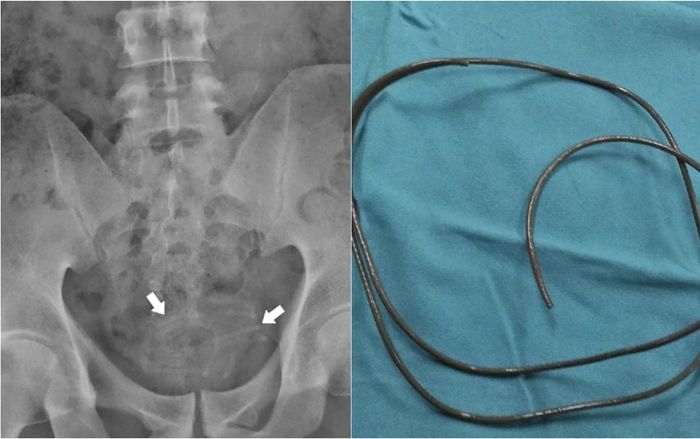

Người đàn ông đau bàng quang dữ dội, đi khám các bác sĩ "tá hỏa" trước hành vi tự thỏa mãn tình dục của anh này.

Bệnh nhân 20 tuổi nhập viện khoa cấp cứu sau khi cảm thấy đau tức ngực, khó thở sau lần thủ dâm.